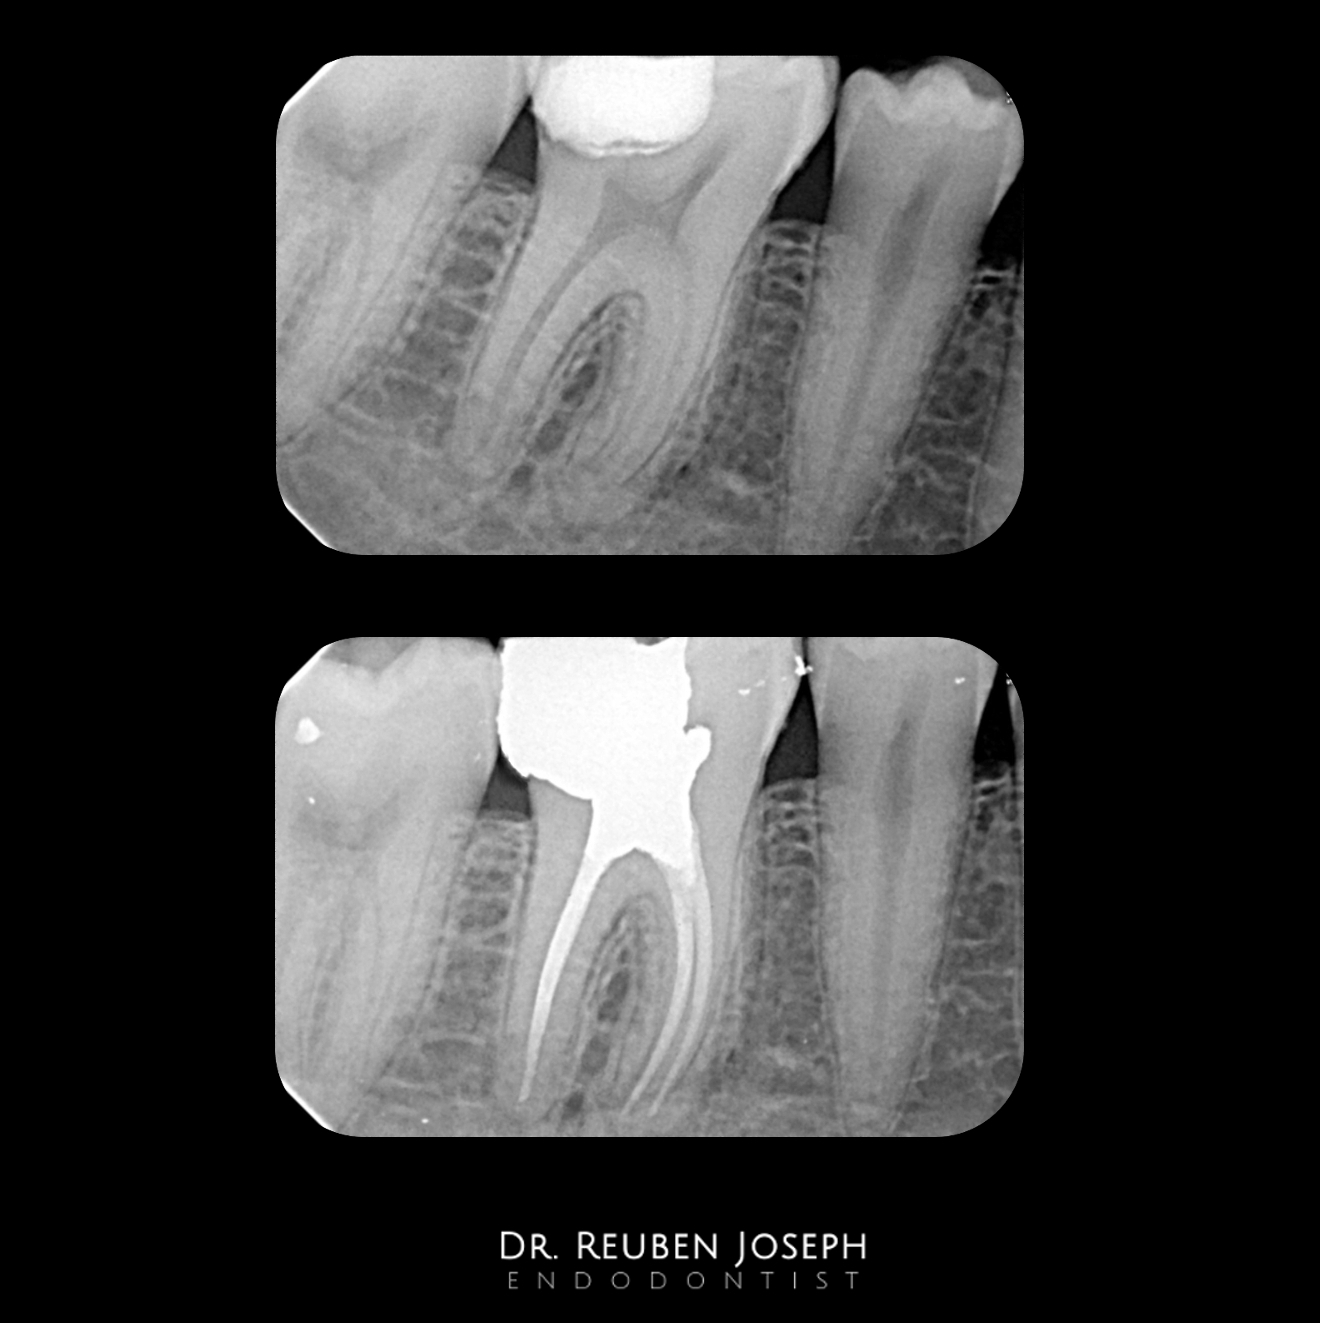

46 – Caries driven access

#46 with caries involving the DL cusp. The amount of tooth structure that would be lost if a conventional SLA access is opted for unimaginable. But i did have SLA in this case as well but from the back 😉